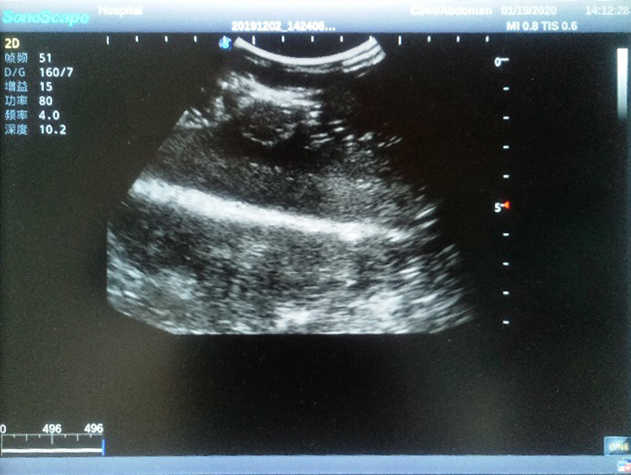

The Breast Ultrasound Examination Model allows users to develop and practice the skills necessary to gain proficiency in breast palpation, using ultrasound for normal and abnormal imaging and biopsy. It simulates adult female breasts with realistic size and appearance.

2)  Each model contains 8 space-occupying lesions of varying sizes, different in touch, elasticity and ultrasonogram

4) Biomimetic material allowing users to see clear and real normal tissues and space-occupying lesions that are hyperechoic, hypoechoic and isoechoic as they would see in the clinical environment